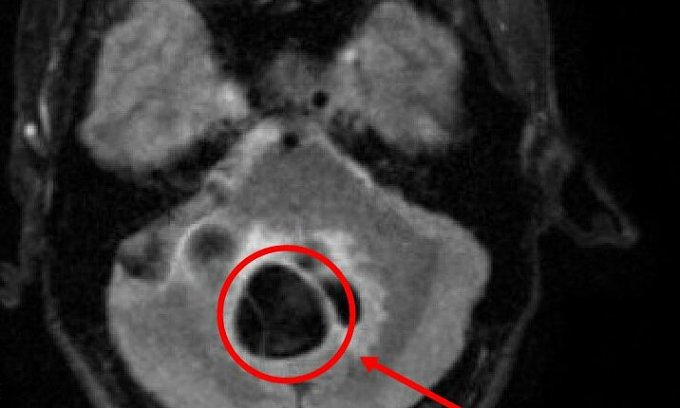

Sau khi bị nhiễm, ấu trùng sán sẽ ký sinh ở nhiều cơ quan trong cơ thể: ở dưới da, cơ, mắt, đặc biệt là não. Não của người bị nhiễm ấu trùng sán lợn có rất nhiều ấu trùng nằm xen kẽ trong nhu mô. Các triệu chứng của sán não thường rất kín đáo cho tới khi người bệnh bị những cơn co giật, chụp cắt lớp sọ não mới phát hiện ra.

Mắc bệnh sán não thường để lại di chứng nặng về thần kinh cho người bệnh. Mức độ tổn thương nặng hay nhẹ phụ thuộc vào số lượng kén sán có trong não. Di chứng sán não ảnh hưởng rất lớn đến chất lượng cuộc sống như suy giảm trí nhớ, người bệnh nhớ nhớ, quên quên như bệnh nhân tâm thần, thỉnh thoảng đau đầu, co giật như động kinh , nặng hơn có thể tăng áp lực sọ não, đột tử.